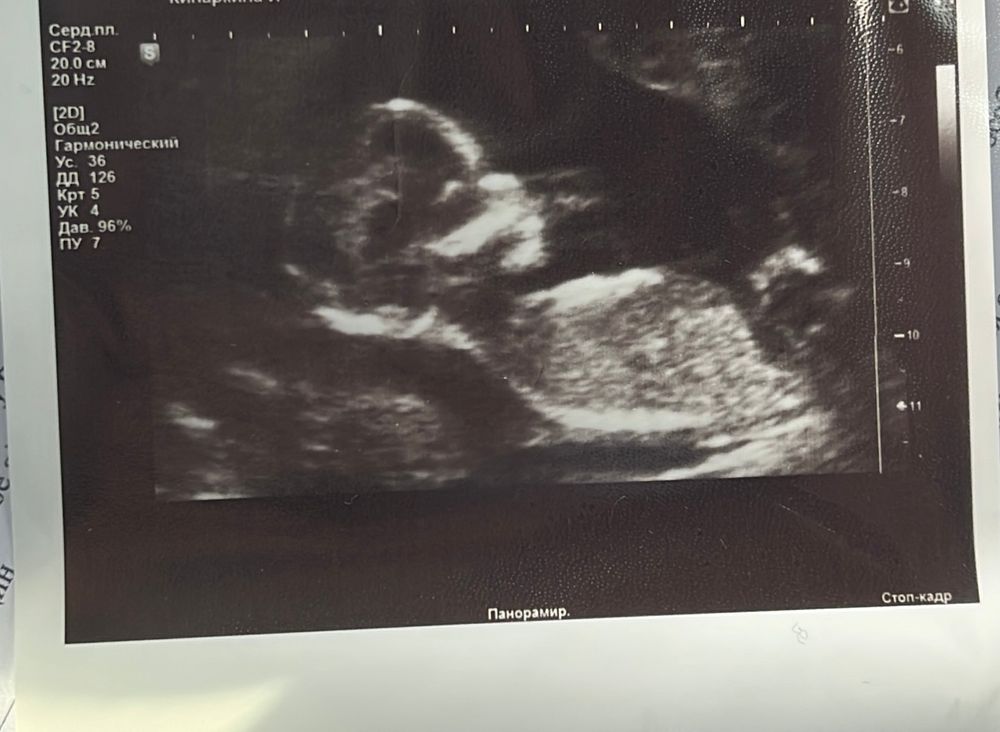

Девочки, ходила на 1 скрининг, врач почти сходу сказала, что предполагает девочку🙈 видите ли вы что- нибудь здесь ? Если бы она не сказала, я бы даже и не задумываясь об этом до 2 скрининга. А теперь стало жутко интересно

На этом фото не видно полового бугорка) неизвестно

Да, тут правда бугорок сложно разглядеть... можно дождаться 15 недели и там должно быть уже хорошо видно)